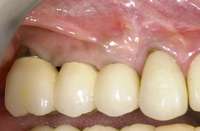

Figure 1G Radiographic confirmation of bone regeneration 8 months after surgery. Figure 1H Radiographic confirmation of implant osteointegration into the new bone 14 months after the initial surgery. Figure 1I. Final implant-supported restoration.

Figure 4C Radiographic view of implant placed simultaneously with sinus bone grafting in site No. 3. Figure 4D Radiographic confirmation of the re-establishment of the sinus floor. Figure 4E Final implant-supported restoration.